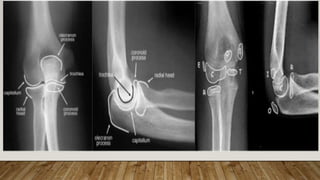

This document discusses radiology and the use of x-rays. It begins with an introduction to radiology and x-rays, noting their importance as the "father of medical investigations." It then discusses anatomy as seen on radiographs and whether x-rays are enough. The document goes on to compare gross views to radiological views, noting what each can and cannot show. It highlights important figures in the development of radiology, from x-rays to CT, MRI, and ultrasound. Specific anatomical structures visible on upper and lower limb x-rays are listed. The document concludes by discussing how pathologies appear on x-rays and the importance of clinical history and knowledge when interpreting radiological images.